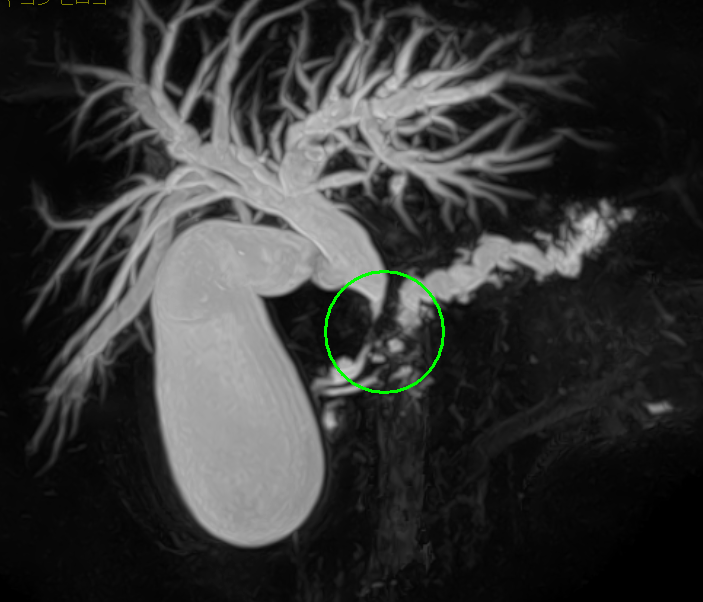

- MRI検査(MRCP)

術前シミュレーション画像(CT画像)